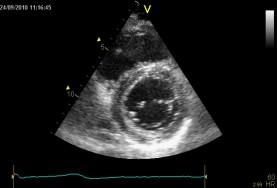

Echokardiografie: LEVÁ KOMORA bez dilatace a hypertrofie, s normální systolickou funkcí a regionální kinetikou kromě D shape, EF LK 55-60%. Diastolická funkce: porucha relaxace LK. PRAVÁ KOMORA FAC PK 18%, TAPSE 13 mm, Vt 9 cm/s, dilatace a hypertrofie PK, těžká prekapilární PH, odhadovaný PASP 90 mmHg, MPAP 55 mmHg, malý perikardiální výpotek

Echokardiografie: LEVÁ KOMORA bez dilatace a hypertrofie, s normální systolickou funkcí a regionální kinetikou kromě D shape, EF LK 55-60%. Diastolická funkce: porucha relaxace LK. PRAVÁ KOMORA FAC PK 19%, TAPSE 17 mm, Vt 9 cm/s, dilatace a hypertrofie PK, těžká prekapilární PH, odhadovaný PASP 130

mmHg, perikardiální výpotek